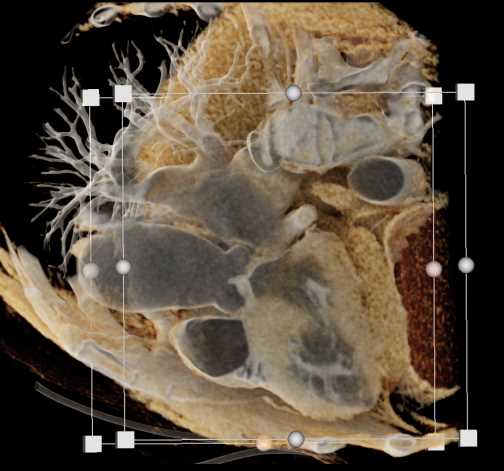

Primary Spindle Cell Carcinoma of the Right Ventricle